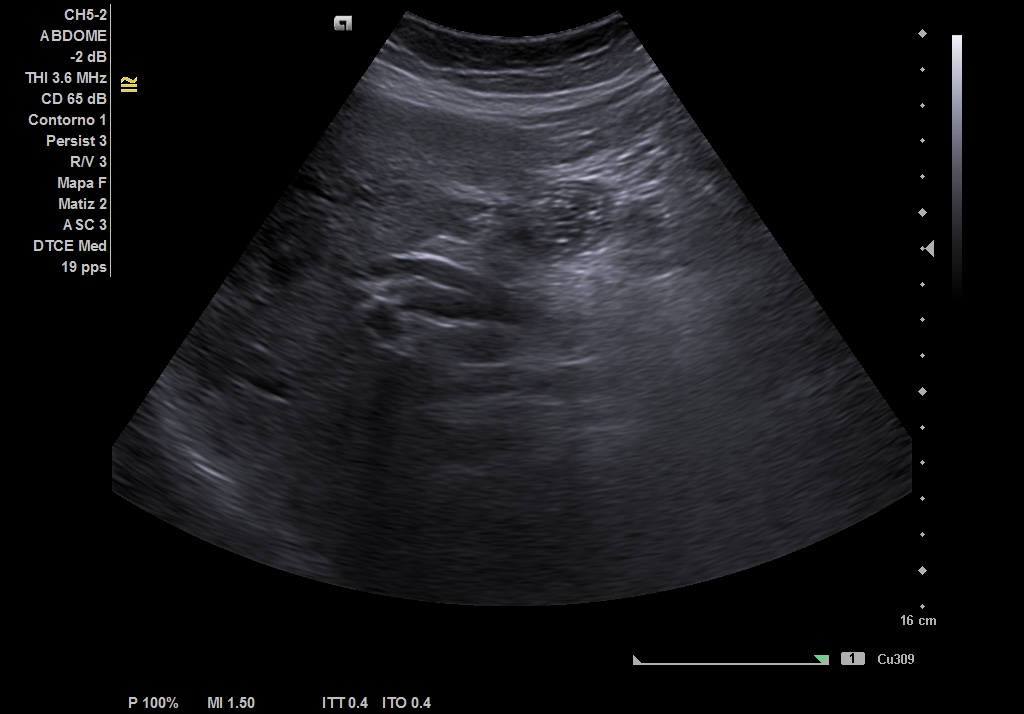

Hallazgos ecográficos

Realizamos ecografía abdominal en el Centro de Salud en el momento de la consulta y visualizamos: Colelitiasis y dilatación de la vía intra y extrashepática sin observar claramente causa obstructiva.

• Nueva ECO de abdomen y colangioRMN en las que se observa: colelitiasis. Vía intra y extrahepática dilatada, sugestivo de coledocolitiasis distal de 5 mm, que se extrae con CPRE.

Pudimos confirmar que se trataba de una ictericia por obstrucción de vía biliar secundaria a litiasis de vesícula, con mismas imágenes encontradas en ECO reglada y en RMN realizadas en centro Hospitalario que las halladas en el Centro de Salud.